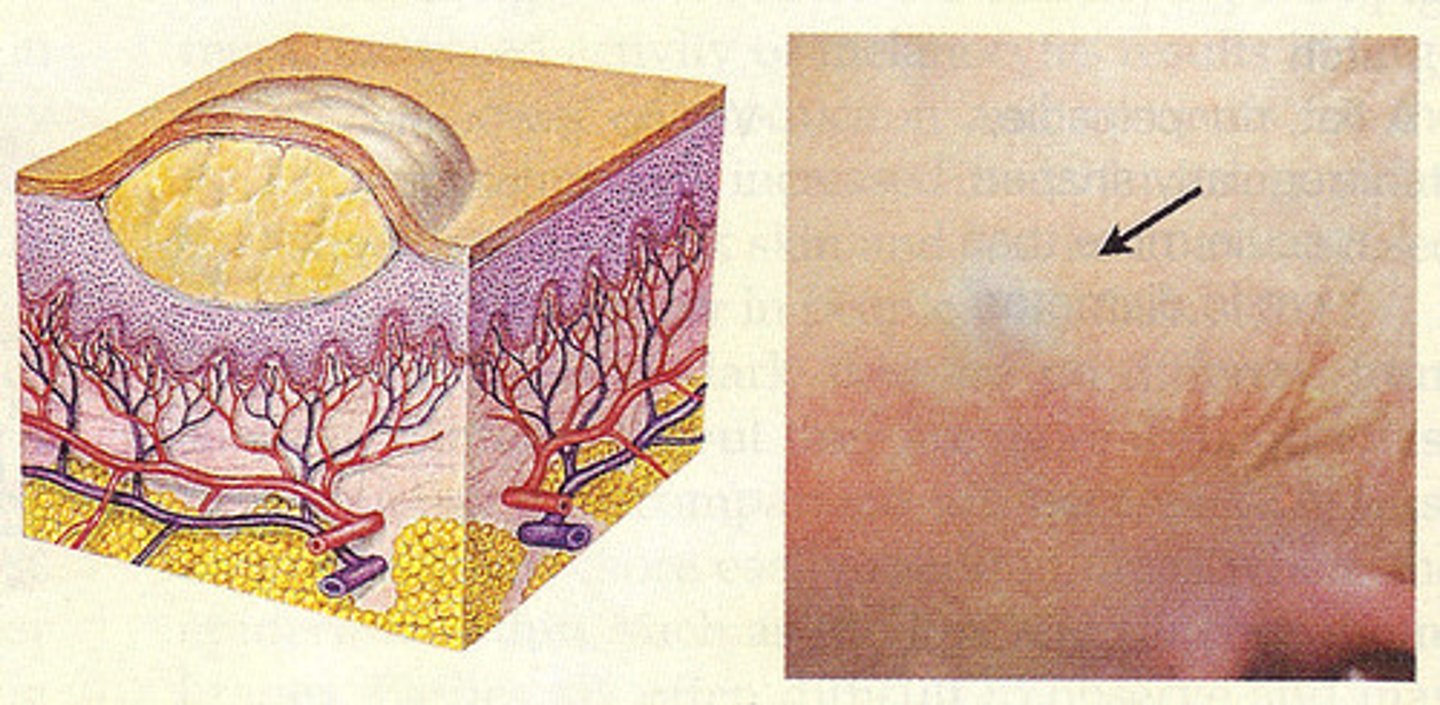

Decubitus Ulcer

skin btw hard places for too long causes compromised blood supply. Epidermis/dermis breakdown and bone can be exposed (bedsore)